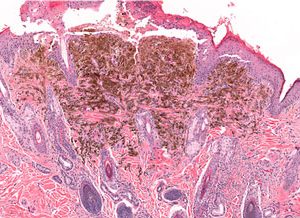

Scientists in the United States have inadvertently uncovered a promising treatment for melanoma that targets the NGLY1 gene.